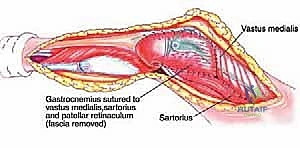

- الرد المفتوح والتثبيت الداخلي (Open Reduction and Internal Fixation - ORIF):

- يتضمن هذا الإجراء عمل شق جراحي لإعادة العظام إلى مكانها الصحيح يدويًا.

- بعد ذلك، يتم تثبيت العظام باستخدام أدوات معدنية صغيرة مثل الأسلاك (K-wires)، أو المسامير (Screws)، أو الصفائح (Plates). تُزال بعض هذه الأدوات بعد التئام العظم، بينما قد تبقى أخرى بشكل دائم.

- تُجرى هذه العملية بعناية فائقة لتجنب إتلاف صفائح النمو قدر الإمكان.

- التثبيت عبر الجلد بالأسلاك (Percutaneous Pinning):

- في بعض الحالات، يمكن إعادة العظم إلى مكانه (بالرد المغلق) ثم إدخال أسلاك معدنية رفيعة عبر الجلد لتثبيت الكسر دون الحاجة لشق جراحي كبير. هذه الأسلاك تُزال عادةً بعد عدة أسابيع.